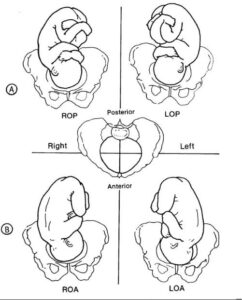

You will hear your doctor state your baby’s position and that will usually consist of 3 letters, but what do they mean? Let’s try to break this down!

L or R

Meaning Left (L) or Right (R) and referring to which side of your uterus your baby’s back is up against.

O

Meaning Occiput (O) and referring to the back of your baby’s head.

A, P, or T

Meaning Anterior (A) referring to your back, near the pubic bone, Posterior (P) referring to your front, near the abdomen or Transverse (T) referring to halfway between Anterior and Posterior.

LOA or ROA

Left Occiput Anterior or Right Occiput Anterior.

LOP or ROP

Left Occiput Posterior or Right Occiput Posterior. These two variations are sometimes referred to as sunny side up.

LOT or ROT

Left Occiput Transverse or Right Occiput Transverse.